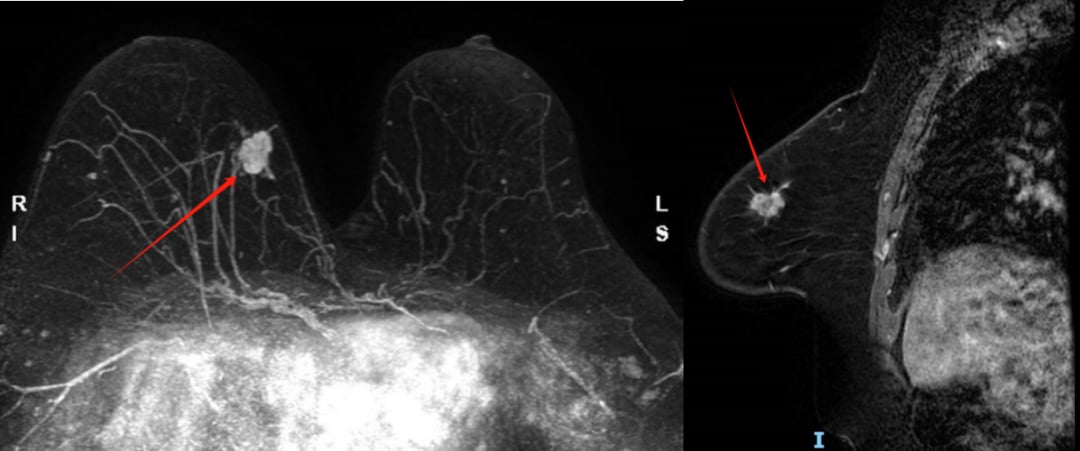

- 乳腺MRI增强扫描:进一步确认了右乳内上象限存在一个约2.1cm大小的不规则肿块,边缘有毛刺,增强后明显强化,同样评为BI-RADS 4C类。

图1 乳腺MRI影像